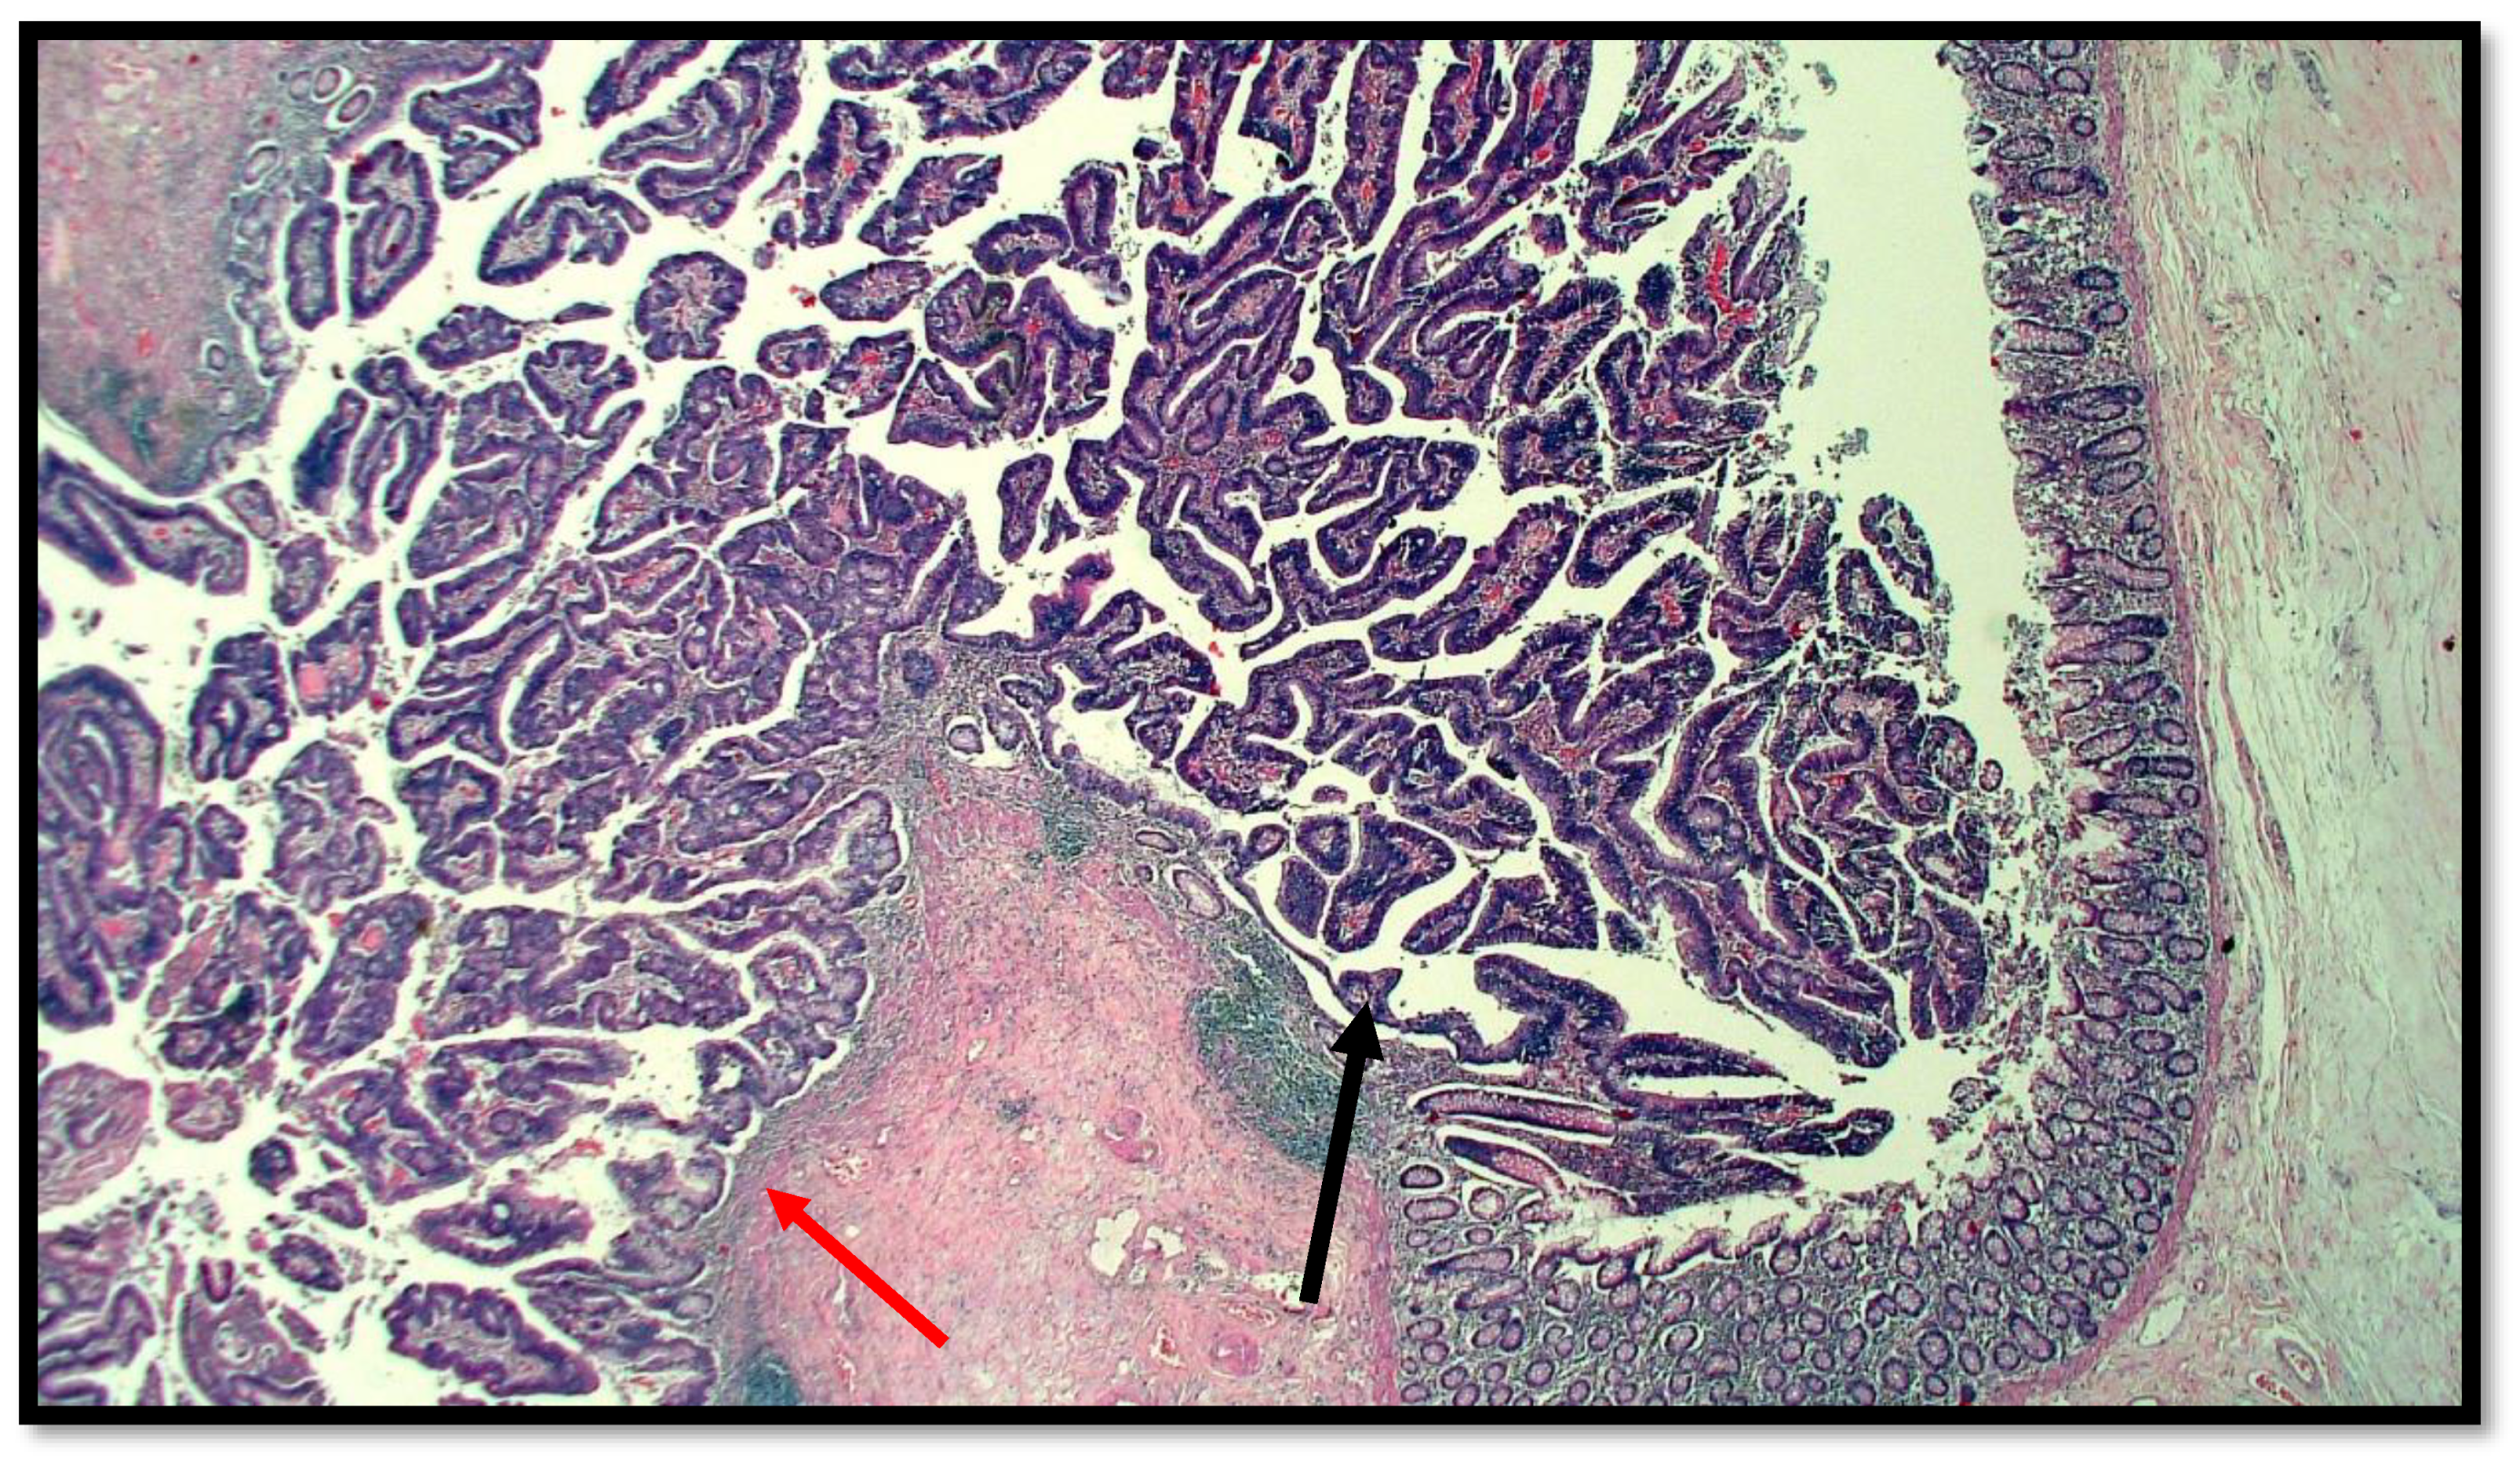

Figure 1.

Histological preparation of intestinal-type adenocarcinoma (black arrow) arising on villous adenoma with high grade dysplasia (red arrow) (hematoxylin–eosin, original magnification: 10×).